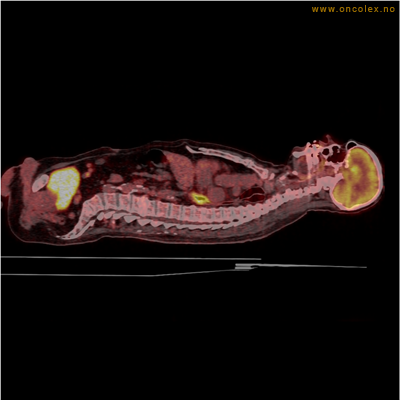

PET/CT (PET: Positron Emisjons Tomografi/ CT: Computer Tomografi) er en avansert nukleærmedisinsk bildetakingsmetode. Metoden er et godt dokumentert, veletablert og svært nyttig verktøy i bildediagnostikk ved kreft. Et PET-kamera gir tredimensjonale bilder av hele kroppen. Integrert CT gjør at informasjonen fra PET blir lokalisert anatomisk nøyaktig.

Kort beskrivelse av undersøkelsen

Gjennom en nål (plastkanyle) i en blodåre i armen vil du få et radioaktivt stoff. Det mest vanlige er radioaktivt druesukker (18F-FDG). Stråling fra det radioaktive stoffet registreres i PET-skanneren og viser hvordan dette stoffet fordeler seg i kroppen. Det normale opptaket av det radioaktive stoffet vil være endret ved sykdomsprosesser. Celler med høyt stoffskite, som for eksempel kreftceller, har økt opptak av sukker. Ved undersøkelsen kan man dermed ofte se større opptak av det radioaktive sporstoffet i kreftsvulster.  Siden CT tas samtidig, kan PET og CT bildene legges sammen og vise nøyaktig hvor i kroppen det økte opptaket er.

Eksempler på funn

Vev som tar opp mer radioaktivt stoff, synes som hvite områder som lyser opp mer i forhold til annet vev som tar opp mindre sukker.